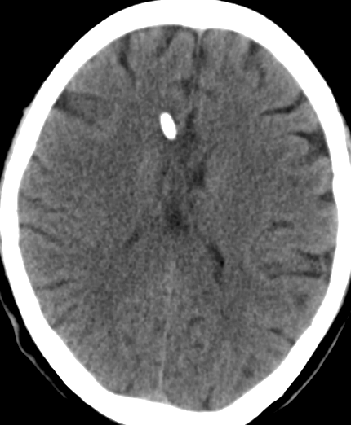

2013-8-2 CT

腰穿脑压240